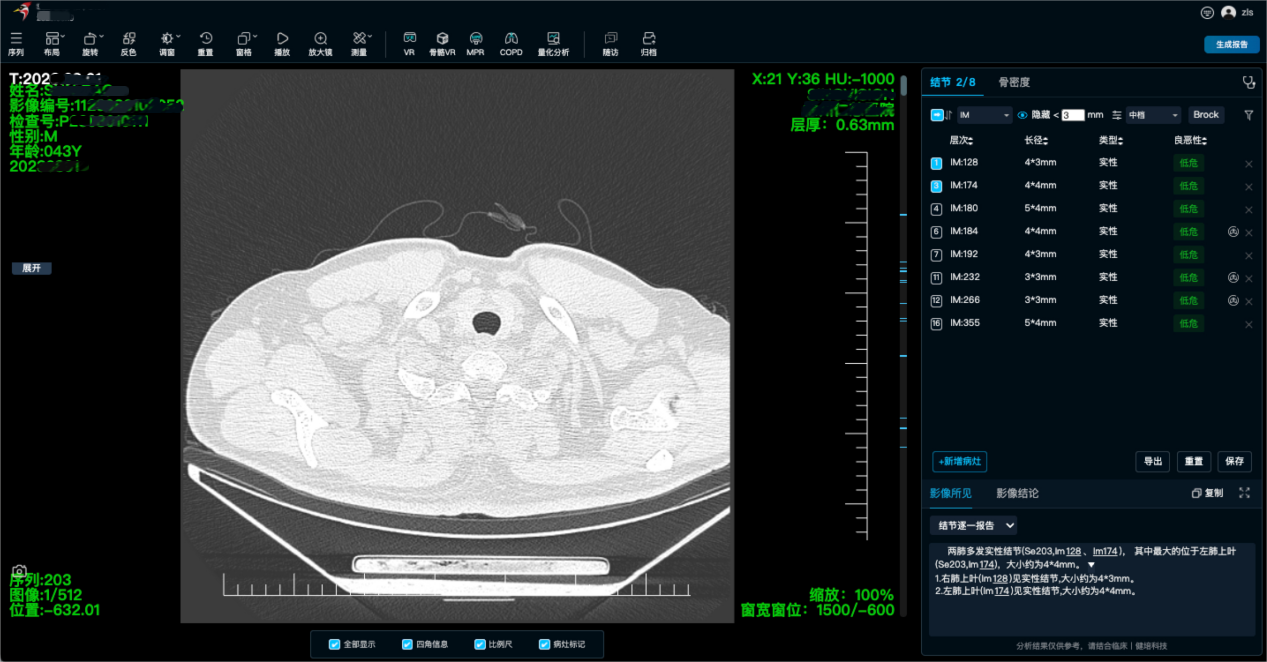

啄醫(yī)生能夠自動對醫(yī)學(xué)影像進(jìn)行閱片和診斷,提供準(zhǔn)確的診斷結(jié)果和病灶信息,醫(yī)生可以根據(jù)啄醫(yī)生的診斷結(jié)果進(jìn)行進(jìn)一步的判斷和治療。覆蓋多種疾病類型,包括但不限于腫瘤、神經(jīng)、心腦血管、骨科、外科、體檢、急診、婦幼、質(zhì)控等場景為中心的AI精準(zhǔn)診斷,覆蓋全身部位、全影像模態(tài)及多元臨床場景。